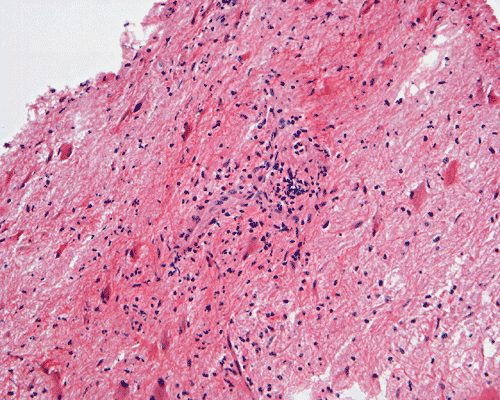

Representative images from the MR studies and specimen are illustrated below:

Panel A to E are MR images. Panel F and G are taken from intraoperative cytologic preparation. Panel H to M are taken from frozen section. Panel N and O are from paraffin section. These sections are stained by hematoxylin-eosin stain. Panel P is immunohistochemistry for neurofilament proteins. Panel Q is stained by Luxol fast blue-Periodic acid Schiff (LFB-PAS) stain.

| DIAGNOSIS: Eosinophilic myelitis. |

Pathology of eosinophilic myelitis

Eosinophilic myelitis is featured by lymphocytic infiltration accompanied by a varying intensity of eosinophils. Both the myelin and axons may be damaged. Axonal spheroids can be seen and indicate primary axonal damage rather than secondary damage following demyelination 14, 15. Destruction of axons in the lesion may well explain the relatively poor recovery of this condition. There is increase in eosinophils in CSF in the our under discussion. However, the CSF studies are normal in two previous studies 14, 15.

The eosinophils play an important role in causing the damages. Infiltration by eosinophils and depositions of activated products of eosinophils are commonly seen in atopic disorders, such as atopic bronchial asthma, allergic rhinitis and atopic dermatitis. The presence of atopic diathesis as well as eosinophilic cationic protein deposition suggests that atopy may represent one of the risk factors for developing eosinophilic myelitis. Eosinophilic cationic protein is one of the neurotoxic proteins released by activated eosinophils Eosinophil cationic protein and other products of eosinophils such as major basic protein have been shown to be neurotoxic. The infiltrating eosinophils may therefore well contribute to the neural damage.

In addition to eosinophils, predominant CD8 T-lymphocytes infiltration is commonly observed 14. Selective infiltration of CD8 T-lymphocytes into the parenchyma, may suggest the critical pathogenic role of these cells, such as a cytotoxic role rather than a secondary suppressive one. In atopic disorders, acute lesions are characterized by predominant CD4 T-lymphocytes infiltration over CD8 T-lymphocytes infiltration, while CD8 T-lymphocytes predominate in chronic lesions. Therefore, the predominant infiltration of CD8 T-lymphocytes seen in the spinal cord may reflect the chronic nature of the lesions.